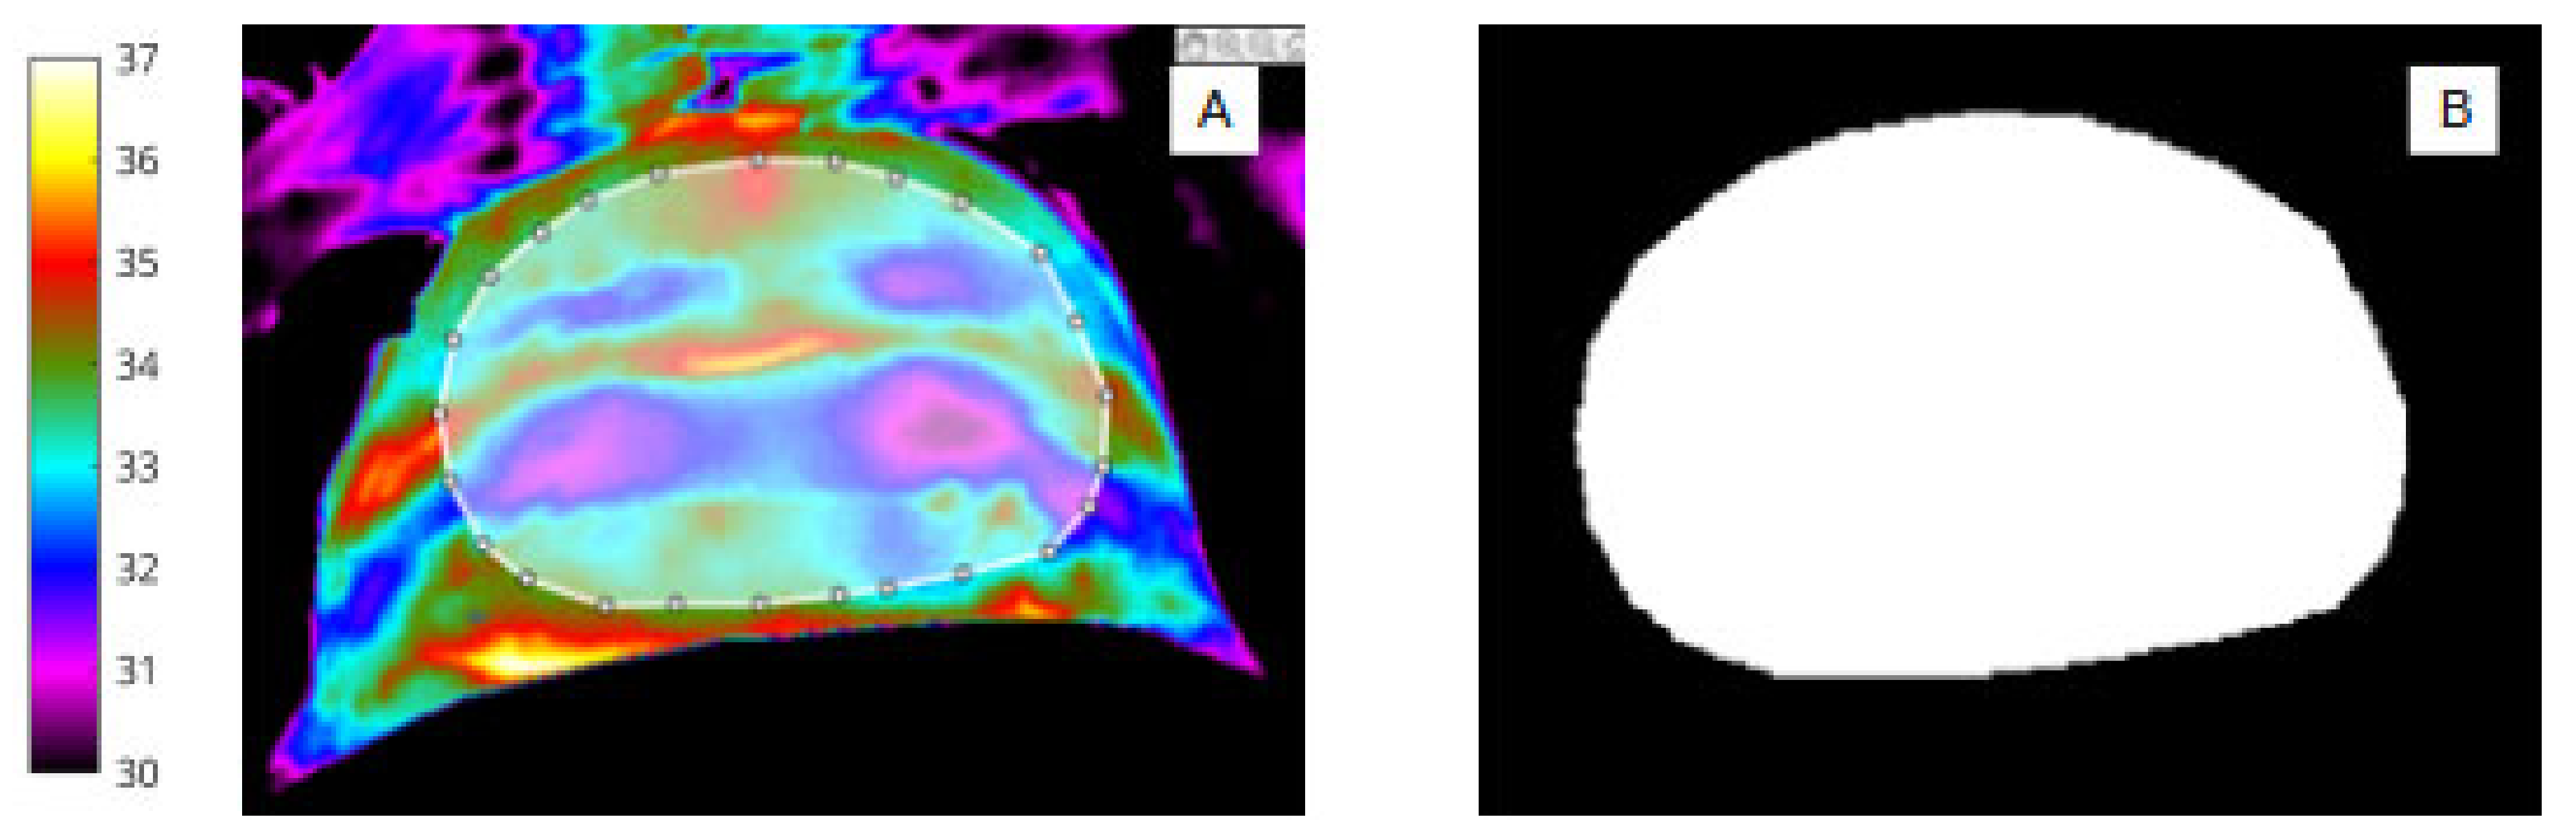

The manual segmentation procedure was performed in MATLAB (R2020a: Mathworks). The image labeller application was used to annotate each ROI label via pixel-level segmentation and creation of pixel masks for the series of 50 abdominal (Figure 1) and wound sites (Figure 2). The segmentation process was performed by two independent researchers, ‘blinded’ to the segmentation process of the other, and was broadly achieved in two stages to

Figure 2.

(A) Infrared image showing segmentation of the abdomen (ROI 1) and white bounding box. (B) Binary mask of abdomen (ROI 1).

2.4. Abdomen and Wound Segmentation

For abdomen (Figure 2A,B) and wound segmentation (Figure 3A,B), the respective regions were identified in infrared and the ROI was selected and cropped. With respect to the surgical site, ROI 2, determining the extent of the area, was often difficult to identify in infrared due to lack of clear anatomical landmarks. To help discern wound area from surrounding healthy skin, reference was made to the corresponding digital image.